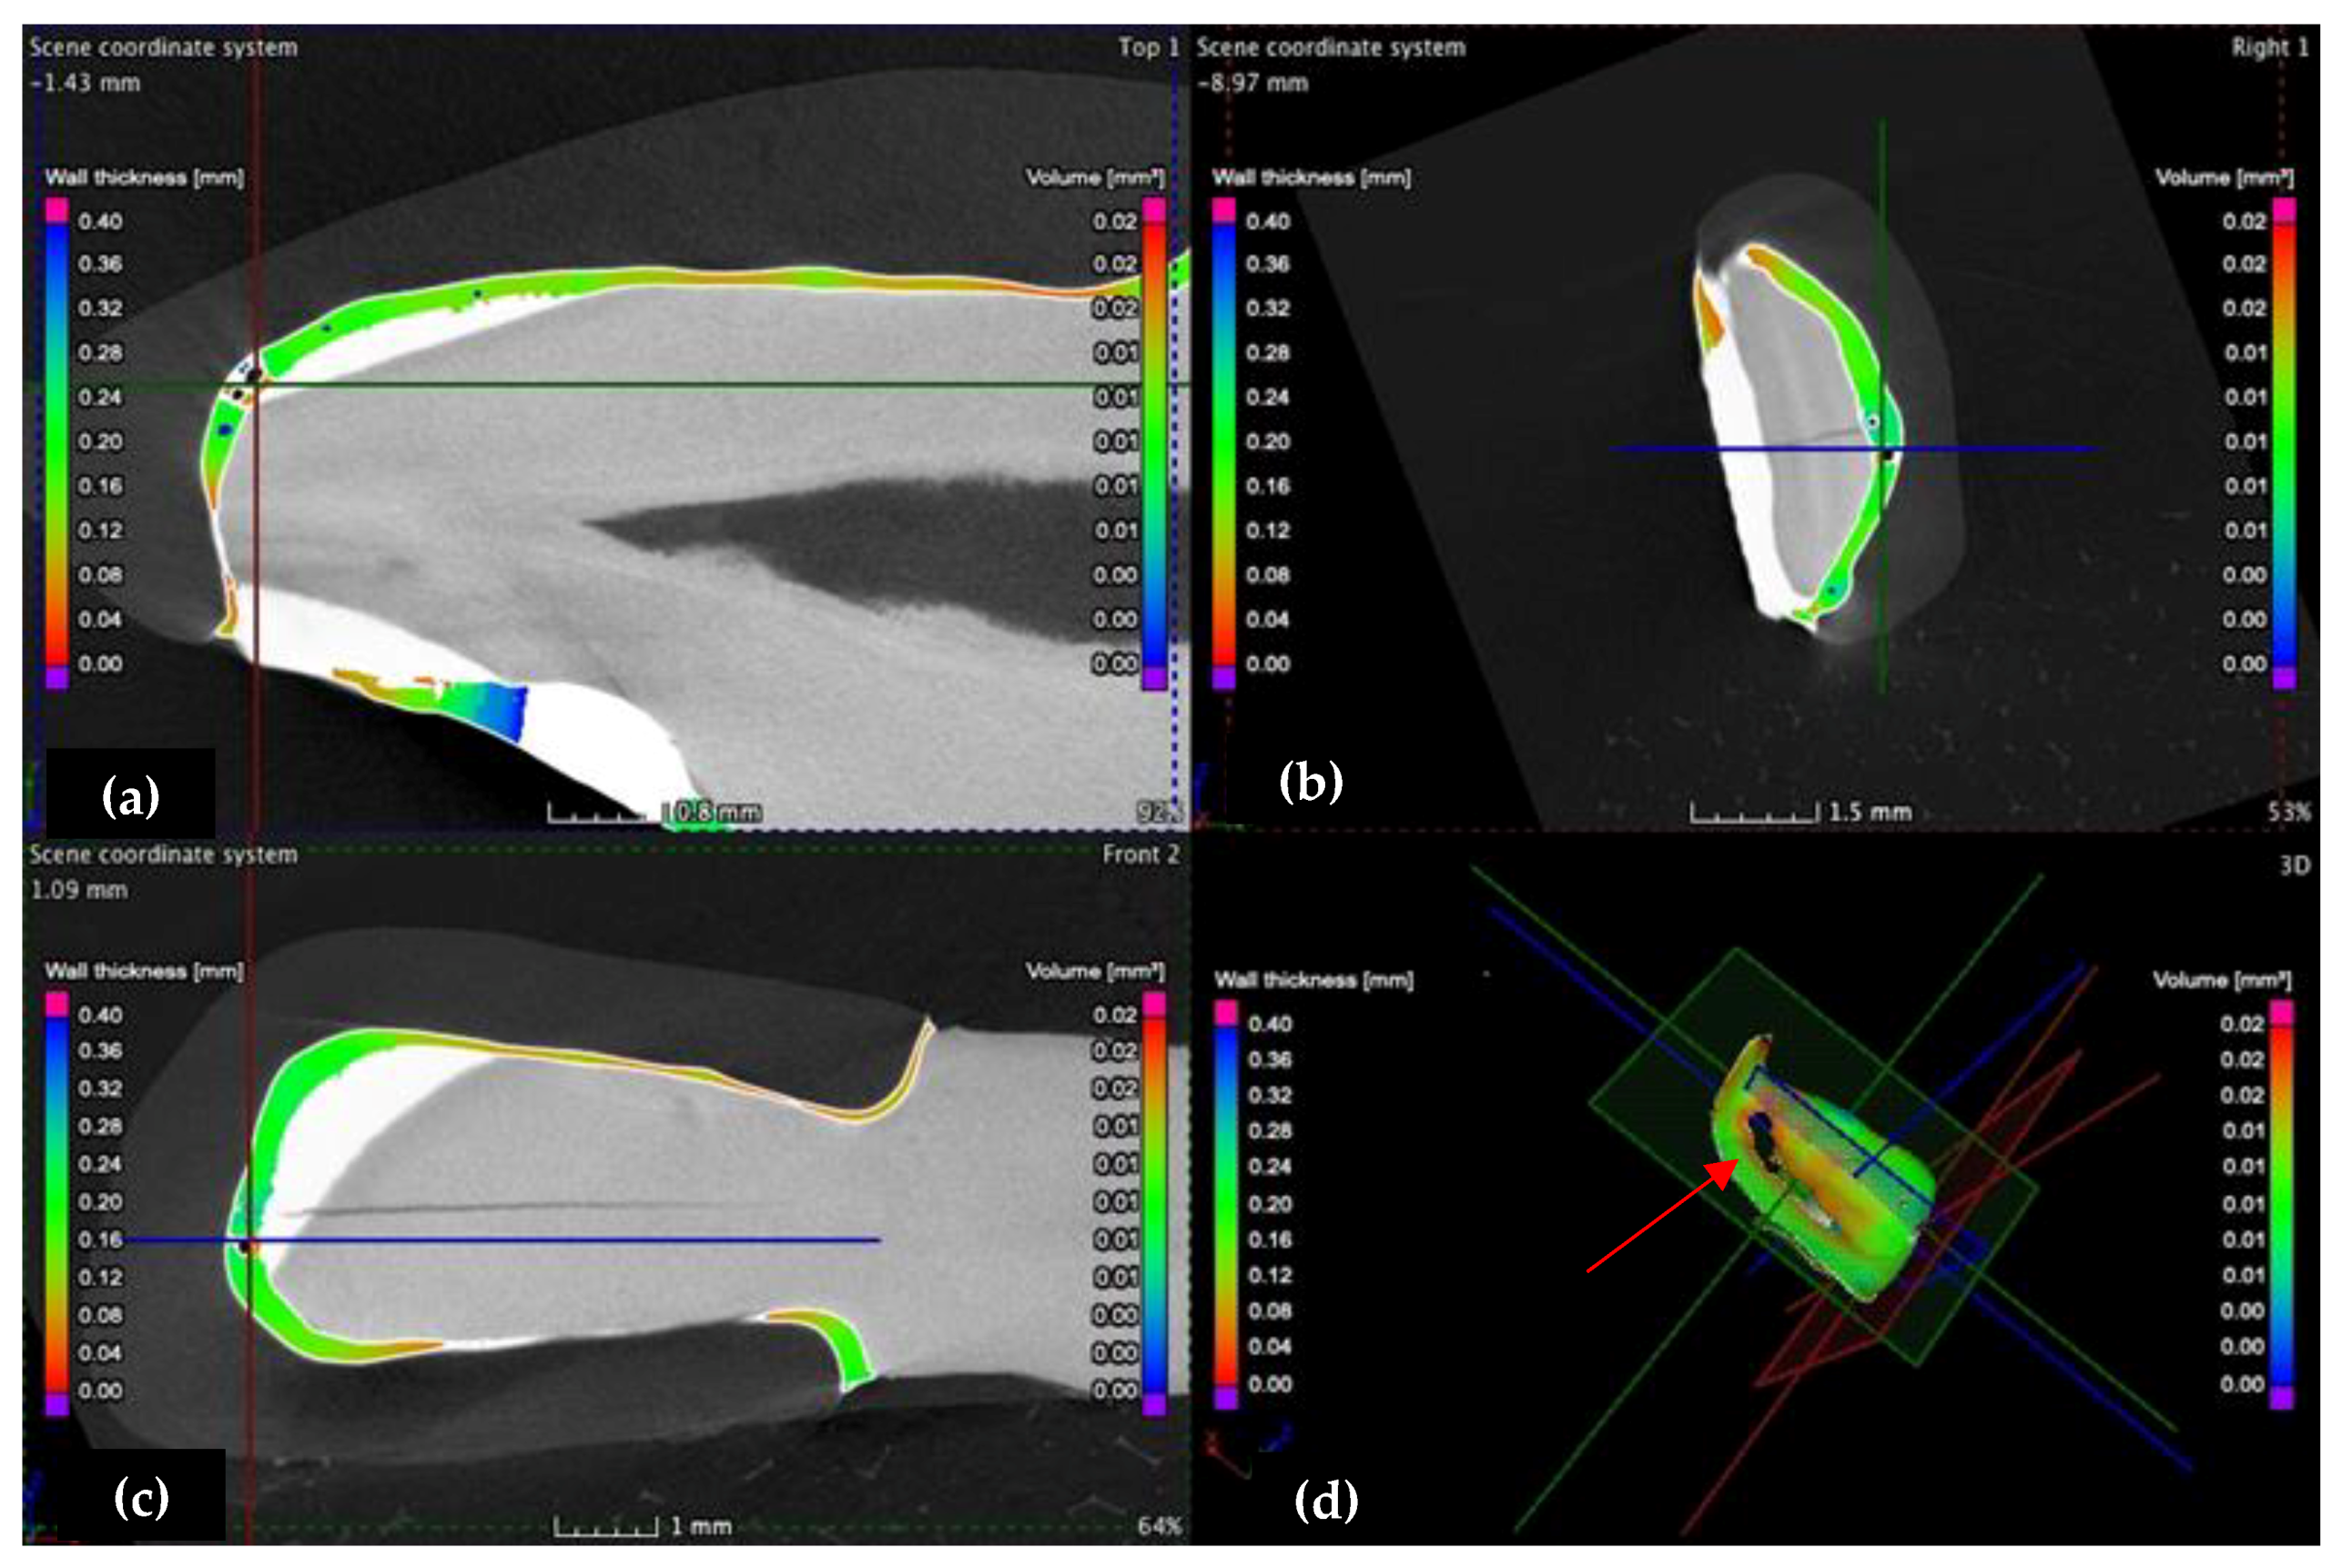

3.2. Micro-CT

3.3. Mathematical Modeling of the Micro-CT Results